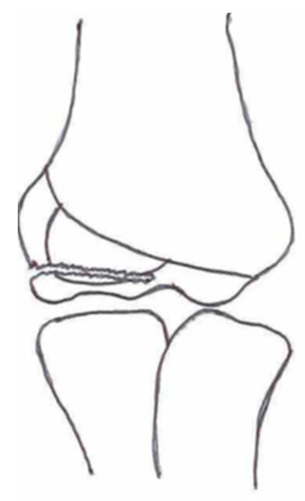

2.3. Classification of Fractures

| Classification | Type 1 (A) | Type 2 (B) | Type 3 (C) | Type 4 | Type 5 |